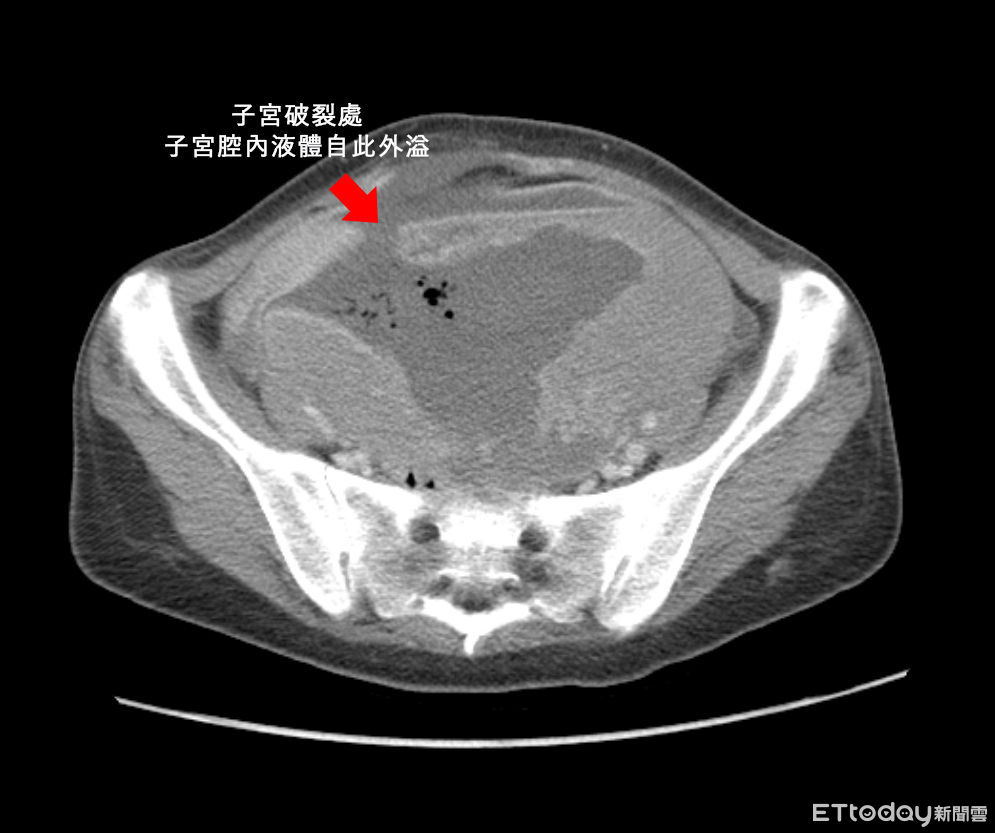

澄清醫院中港院區婦產科醫師黃兆麒表示,婦人到院時,血紅素已掉到2.7,正常值是12以上,不是一般的貧血現象,再緊急做電腦斷層檢查。一般子宮長約8公分、寬約5公分,但檢查發現她的子宮肌瘤有17公分大,且已經有子宮破裂跡象,經緊急開刀摘除子宮,同時發現因腹壁筋膜受損,形成腹壁疝氣,必需再做二次手術修補筋膜層。